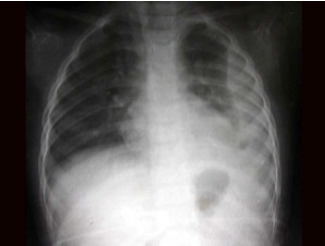

36、单项选择题

男2岁,左侧胸痛、气促,如图所示,最可能的诊断为()

55、单项选择题

男,16岁,长期的骨骼肌肉畸形,听力障碍,结合图像,最可能的诊断是()

A.马方综合征

B.成骨不全

C.肾性骨病

D.甲状旁腺功能亢进

E.维生素D缺乏症